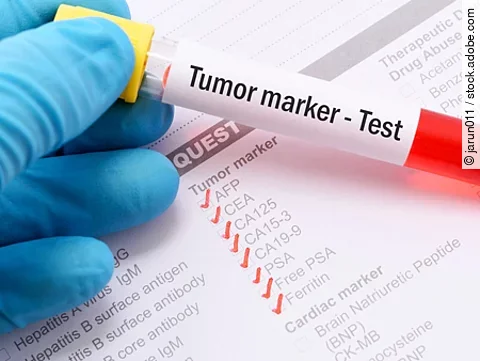

Rezidivrisiko soll reduziert werden

FDA lässt Nerutinib zur adjuvanten Brustkrebs-Therapie zu

17.08.17

| News

| Rx aktuell